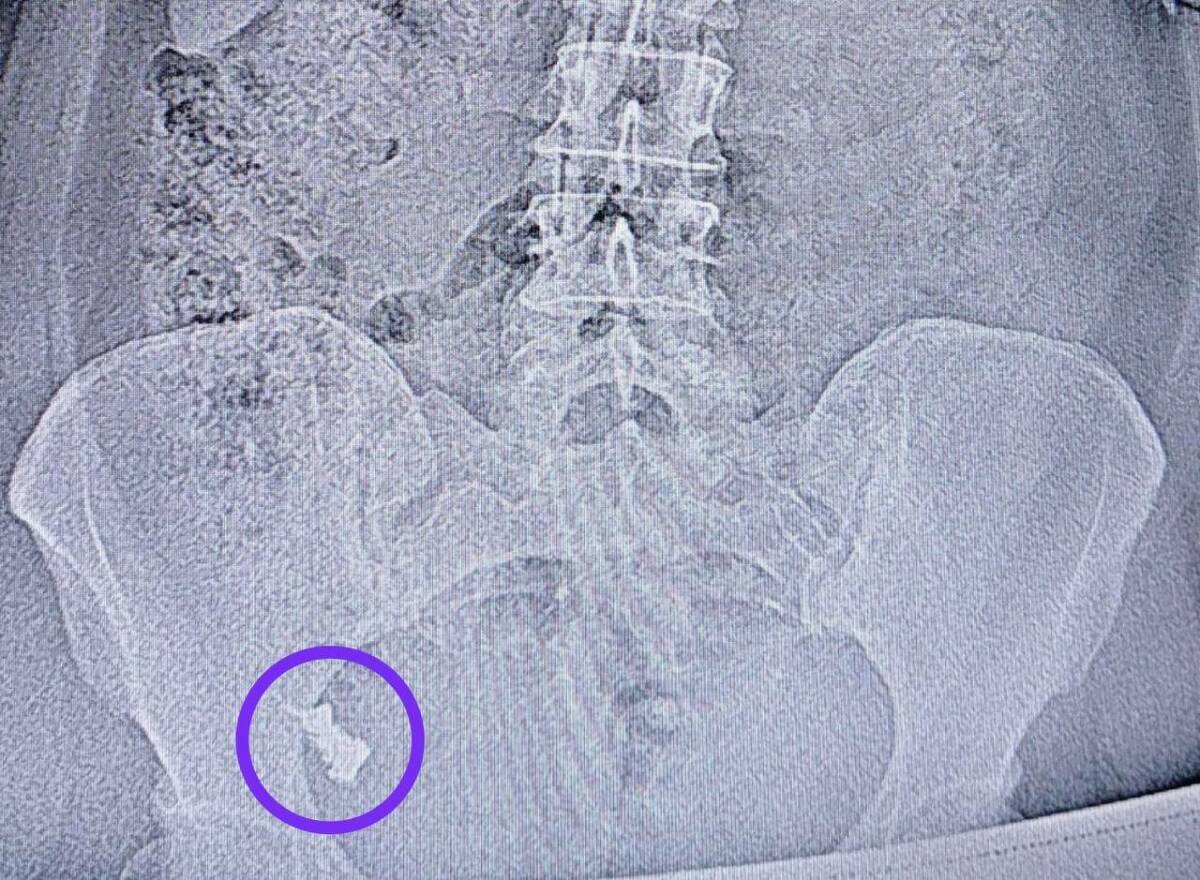

Спустя неделю женщину госпитализировали в хирургическое отделение №1, поскольку протез застрял в области перехода тонкой кишки в толстую.

Врач-эндоскопист Наиль Исхаков во время колоноскопии удалил протез. Процедуру делали под контролем анестезиолога-реаниматолога Елены Чуенковой, поскольку протез находился уже в труднодоступном месте.